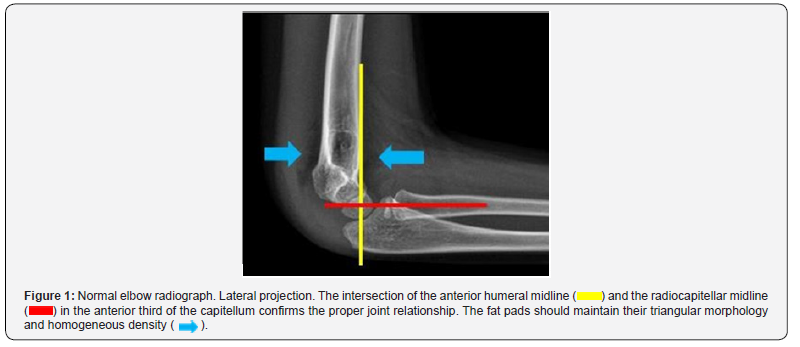

Elbow trauma in children is the second leading cause of emergency department visits, with supracondylar fracture being the most common diagnosis, affecting between 5 and 7 years of age [1]. Correct identification, classification and timely intervention will reduce morbidity, as consolidation in the immature skeleton of children occurs quickly. They usually affect the area most proximally to metaphysis, i.e., the hypertrophic, vascularized and provisionally calcified area with a high risk of neurovascular complications [1,2]. Clinical suspicion begins with a history of trauma in forced extension (more than 97% of cases), while the flexion type is much less common; as well as data on physical examination such as functional limitation, exclusion of the limb and edema [1,3]. The diagnosis supported by diagnostic images is made by means of elbow radiography, which consists of anteroposterior and lateral projections, the latter being the most important and relevant in the diagnosis (Figure 1) [4]. For the imaging findings we first familiarized ourselves with the identification of the ossification nuclei, facilitated by the CRITOE menometechnics (Figure 2), (Capitellum, radius, internal epicondyle, trochlea, olecranon, external epicondyle) with their age of appearance 1-3-5-7-9-11 years, respectively [5]. Findings associated with trauma include the fat pad sign, which is defined as bulging and/or effacement of the fat pad, joint effusion, loss of joint relationship and most importantly the fracture line for subsequent Gartland classification. Complementary tomography is relieved for cases with negative radiographs and clinical suspicion as well as for surgical planning due to complexity in some cases [1,6].